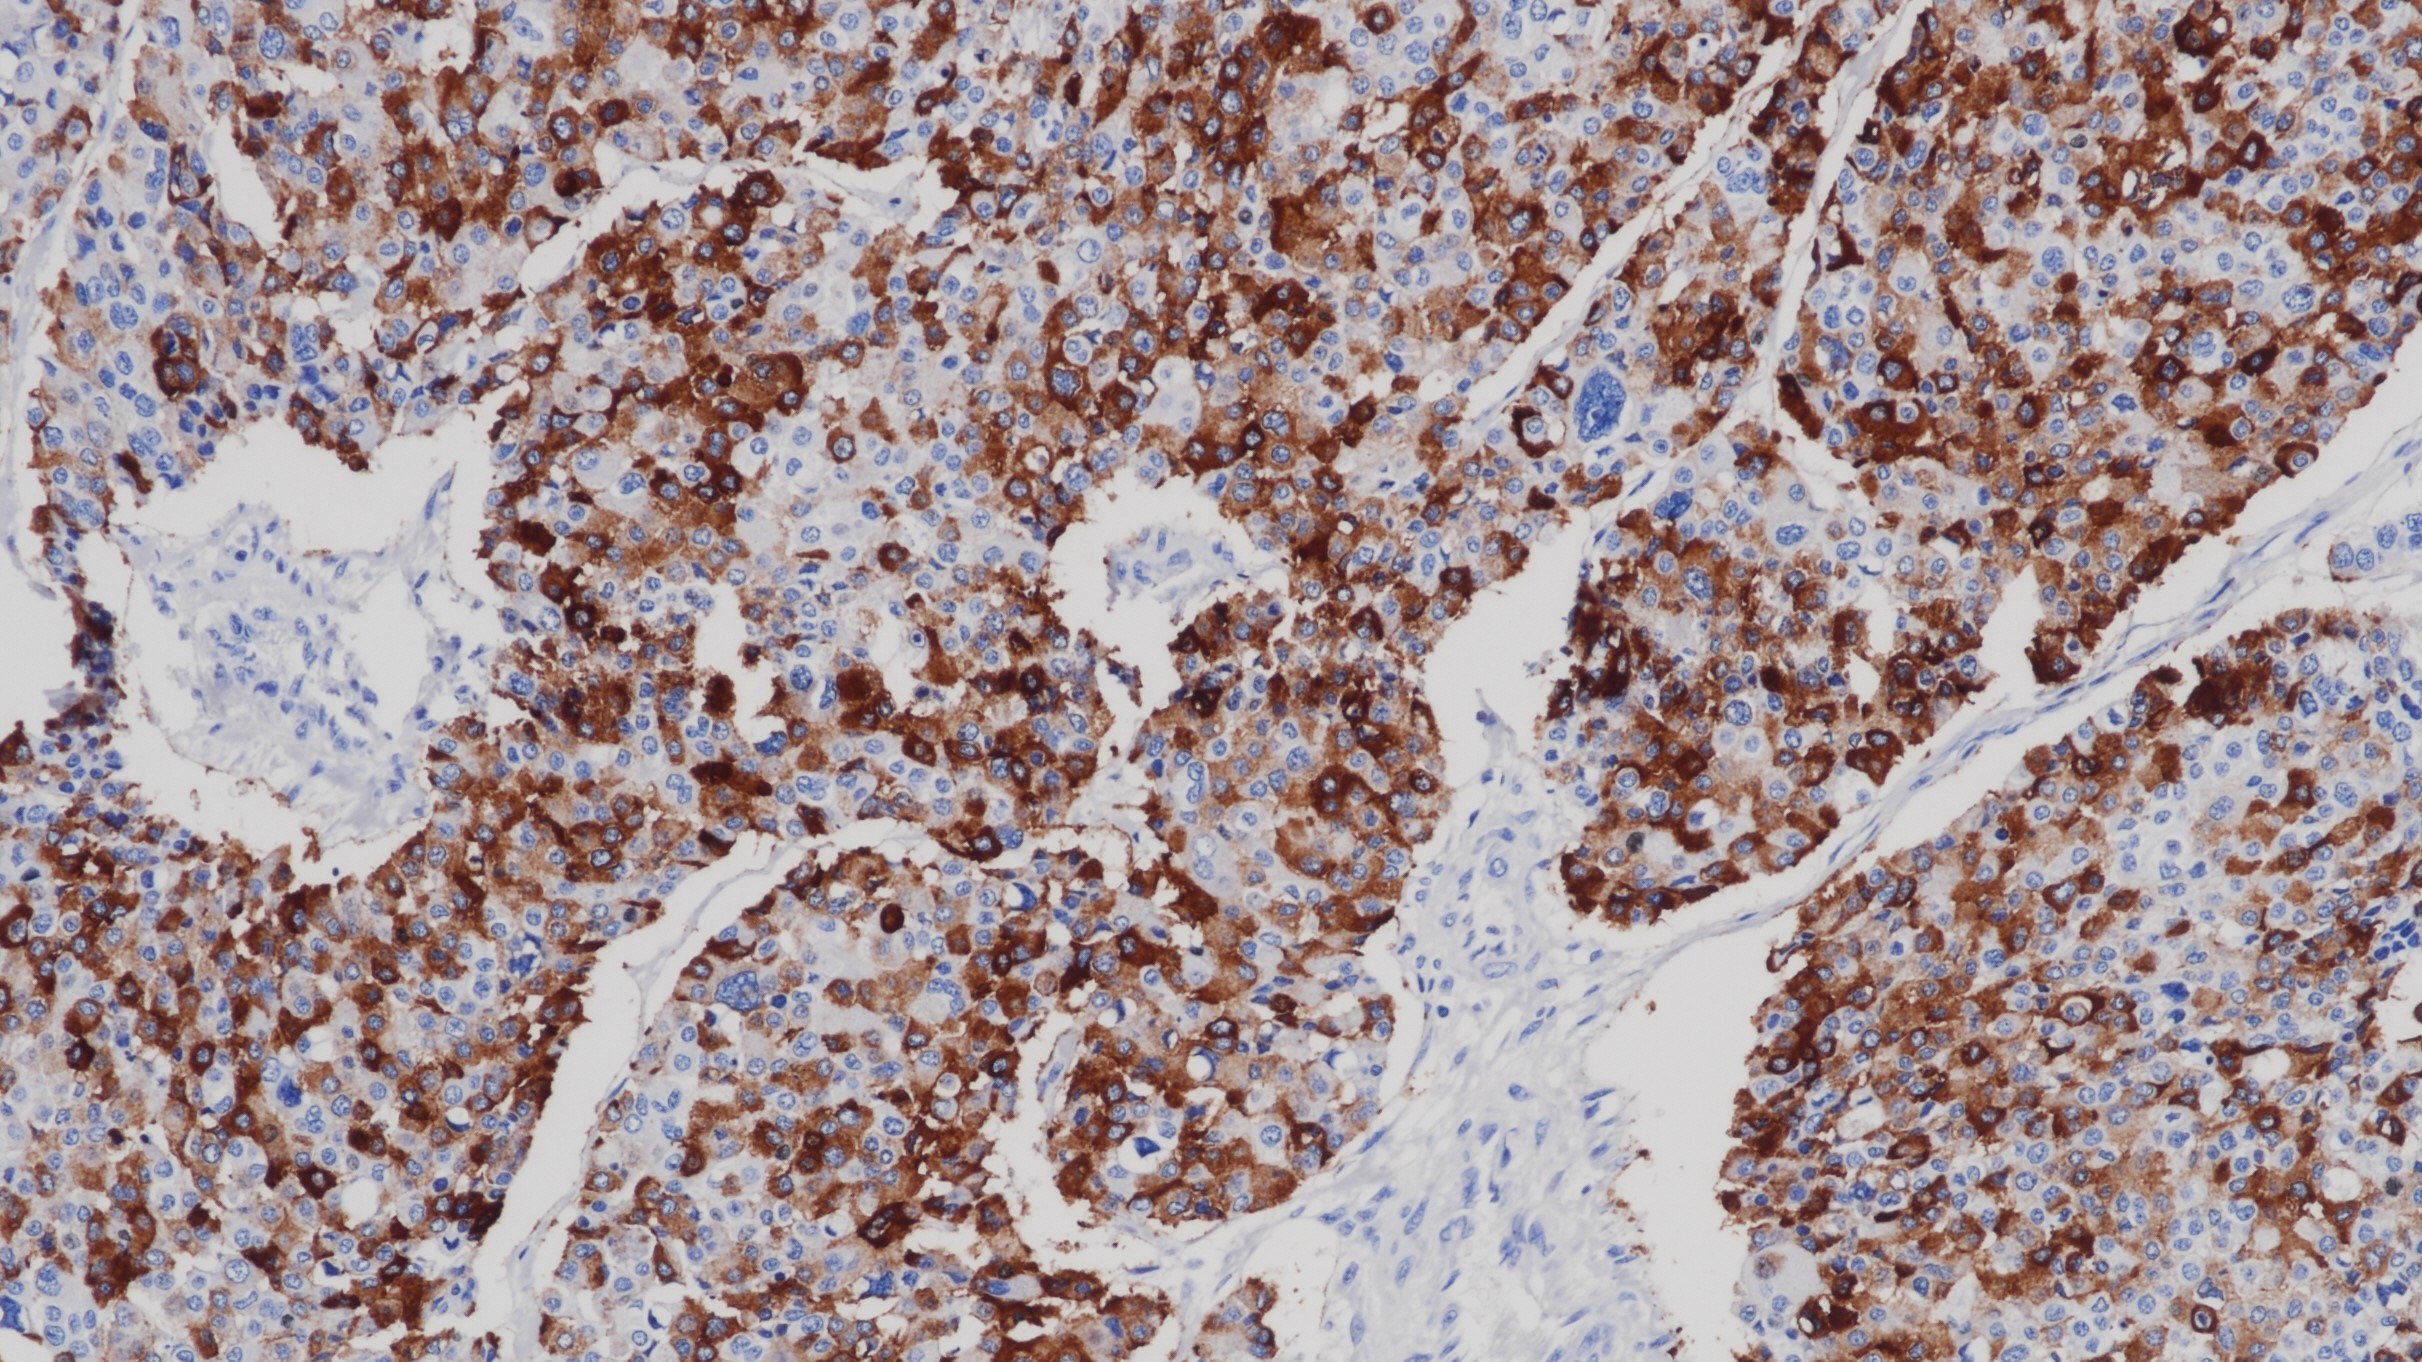

前列腺癌 AMACR(CMA158)染色

AMACR/p504s是脂肪酸支链β氧化酶中的重要酶。AMACR在前列腺腺癌中高表达,而在良性前列腺组织则不表达。 AMACR的表达也可检测前列腺癌前病变,如:前列腺上皮内肿瘤(PIN)和非典型腺瘤增生。AMACR作为阳性标记连同作为阴性标记的基底细胞(34bE12/P63)一起染色,有助于确症PIN和前列腺癌小病灶。